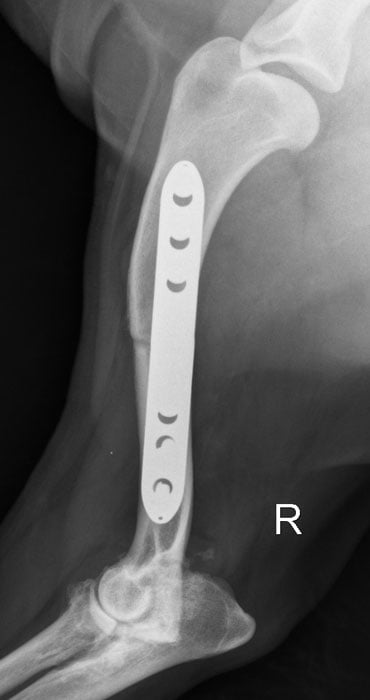

Die 'SHO' ist ein fortgeschrittener chirurgischer Eingriff, der nur an wenigen Kliniken weltweit durchgeführt wird. Hierzu wird der Oberarmknochen durchtrennt und in einer speziell neuen Position durch eine besondere Stufenplatte fixiert. Hierdurch wird das Gewicht der Vordergliedmaße von der erkrankten medialen Seite mehr auf die gesunde laterale Seite verlagert, ohne dabei diese zu überlasten. Durch die abnehmende Gewichtsbelastung auf das mediale Kompartment des Gelenks kann sich der Gelenkknorpel in Folge regenerieren und die Gleitfähigkeit des Gelenks verbessern.